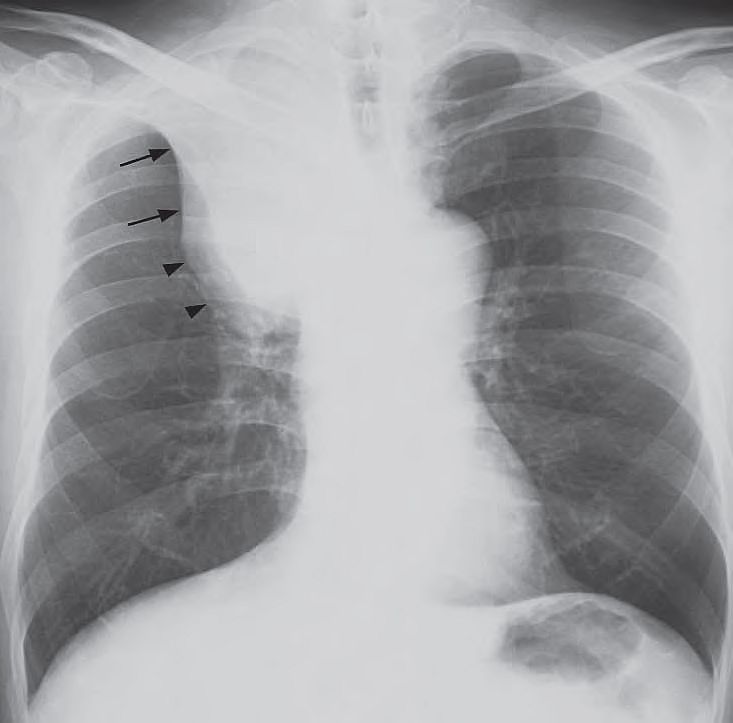

- Opacity with a sharp well-demarcated lateral border (arrows) in right upper zone with lack of air within the abnormality.

- Focal convex bulge at the apex of the abnormality.

- Hyperinflation of the right lower lobe.

- Elevated right hemidiaphragm.

The ‘Golden S sign’ – collapse of the right upper lobe with a well demarcated lateral border formed by the elevated horizontal fissure (arrows), and a focal convex bulge at the apex due to the centrally located bronchogenic carcinoma (arrowheads).